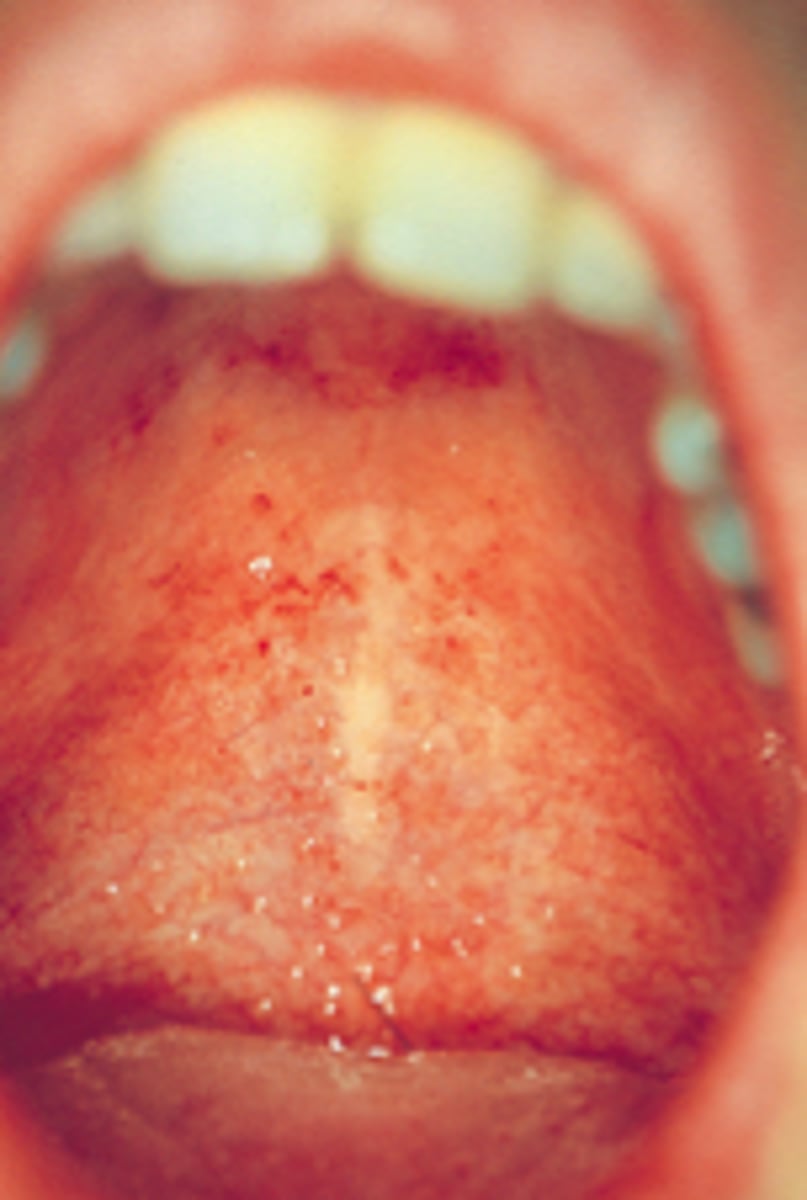

What are Koplik spots?

An indicative sign of measles infection that appears as tiny erythematous macules with white necrotic centers on the buccal mucosa